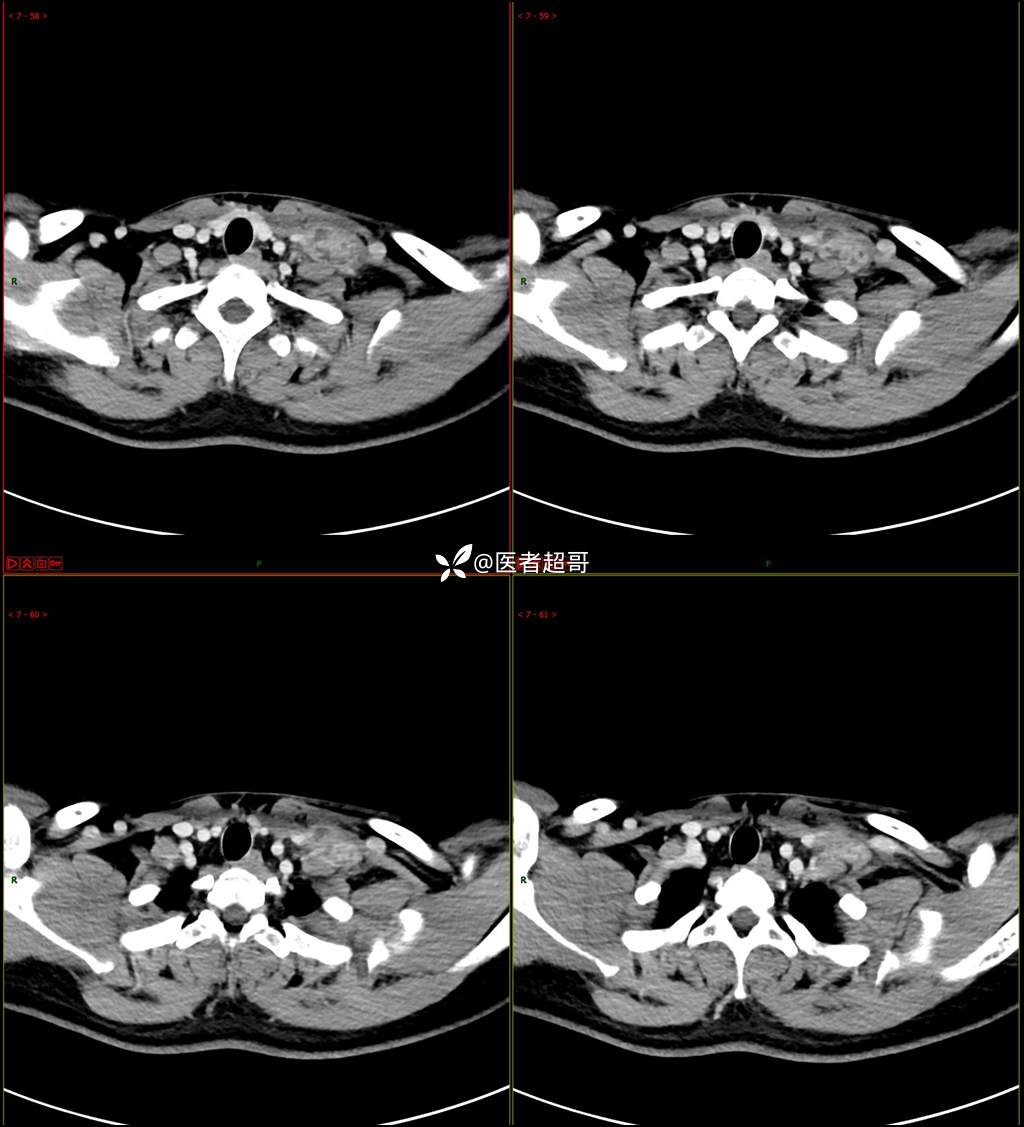

现病史:患者自述10余天前无意中发现左侧颈部一肿物,颈部活动时、进食时伴疼痛,无发热,患者前往人民医院就诊,给予输液治疗(头孢呋辛钠2g bid 硫酸阿米卡星0.4g qd、)10天,患者感肿物轻微变小,后患者为求进一步治疗,昨日来我院门诊就诊,给予颈部彩超示:左颈部实性肿物,神经来源?,左颈部肿大淋巴结;颈部ct平扫+强化示:左侧锁骨上区占位,神经鞘瘤?双侧颈部多发淋巴结;门诊以“局部肿物”收治入院,患者自患病以来,神志清,精神可,饮食睡眠可,体重无明显变化,二便正常。